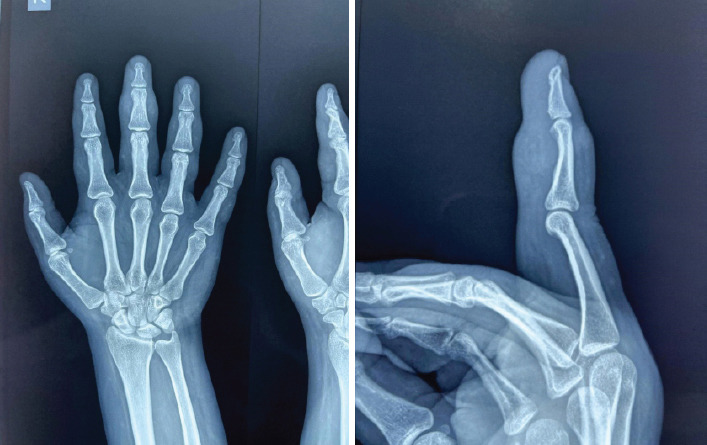

Case report: We present the case of a 26-year-old female who reported sudden onset pain and swelling in her right middle finger without any history of trauma. Initial radiographs were soft-tissue swelling noted. Magnetic resonance imaging revealed a benign soft-tissue lesion suggestive of TGCT. Surgical excision followed by histopathological examination confirmed the diagnosis. Post-operative recovery was uneventful, and the patient regained full function without recurrence at the 6-month follow-up.